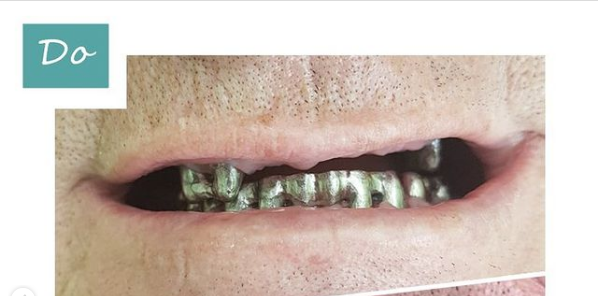

Установка коронки на зуб

Обратился пациент, с вопросом боли и смены старых протезов (коронок) на современные. Под старый протезы, со временем (учитывая убыль десны), стала попадать пища, слюна, тем самым стала разрушаться эмаль оставшихся зубов. Для спасения зубов была изготовлена новая конструкция, рассчитанная на длительный период эксплуатации!